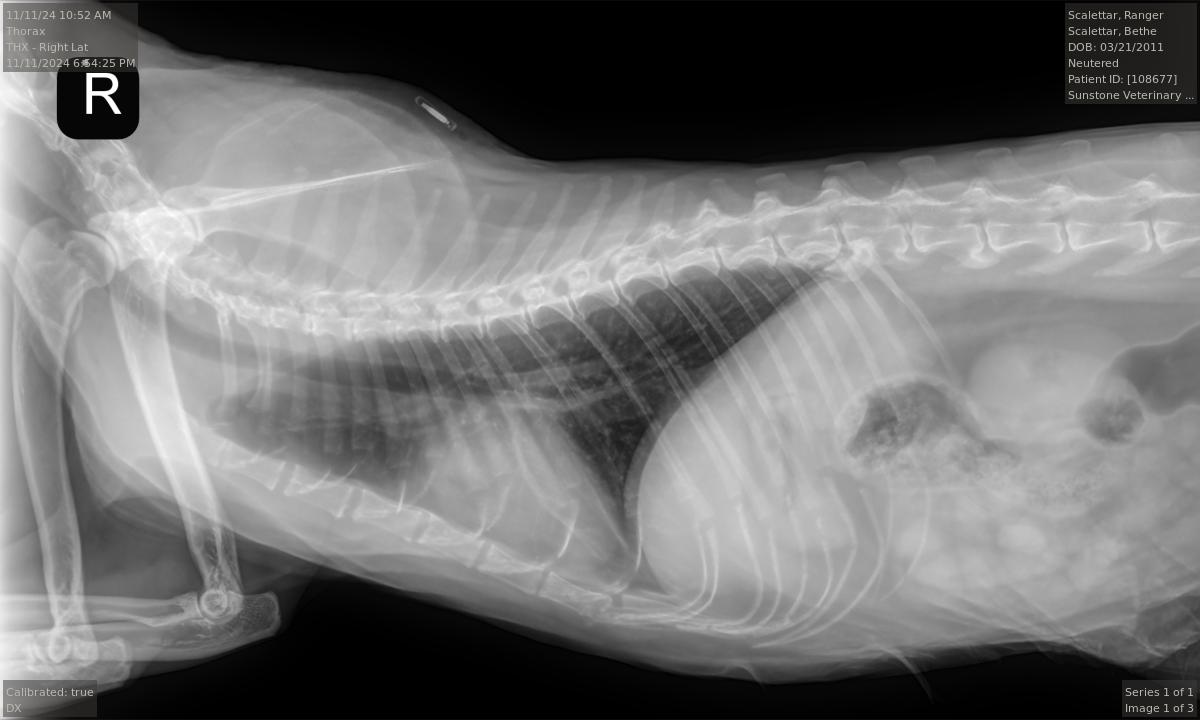

Veterinary diagnostic radiographic studies of the thorax and/or abdomen typically include at

least two projections: (1) a right (R) or left (L) lateral view, and (2) a ventrodorsal (VD) or

dorsoventral (DV) view. Right and left lateral views are taken with the animal lying on its right

(R) or left (L) side, respectively. Ventrodorsal and dorsoventral views are taken with the animal

lying on its back (VD) or stomach (DV), respectively. Radiopaque markers (e.g., “L” and “R”) are

placed near the animal to distinguish the views.

Projection radiographs lack depth information because the intensity of each point in the image

is a superposition of all structures along a given straight-line X-ray trajectory through the body.

However, by taking images along at least two orthogonal directions (e.g., R or L AND VD or DV),

the veterinarian can obtain three-dimensional information from the two-dimensional images.

For example, the pairs of superimposed ribs visible in the accompanying L and R radiographs

are visible as separate left and right ribs in the VD view. Taking both L and R views, or both VD

and DV views, can yield additional information.

The radiologist stated that the Ranger's radiographs were largely normal for an older cat. In

particular, they show arthritic changes in both elbows and the middle back. However, the

images did not show any abnormalities in the lungs and only mild, if any, enlargement of the

heart. Overall, these were good results.